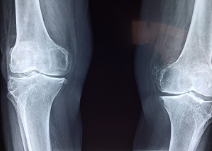

연골은 부드러운 움직임을 위해 뼈 사이에 존재하는 결합 조직으로 인간의 근골격계를 구성하는 중요한 요소 중 하나입니다. 연골은 충격을 흡수하고 뼈 마찰을 줄여 관절 부상을 예방합니다. 또한 연골은 관절에서 분비되는 활액에 영양분을 공급받아 영양분을 흡수해 생존한다. 그러나 나이가 들어감에 따라 연골 조직이 퇴화하고 내구성과 탄력성이 떨어지게 되어 관절염과 같은 상태로 이어질 수 있습니다.

무릎 연골 손상은 대개 점진적으로 악화되며 갑작스러운 부상이 아니라 장기간의 긴장, 부적절한 자세, 반복적인 활동, 무릎 주변 근력 약화 등 일상적인 활동에서 발생합니다. 무릎 연골 손상의 증상은 다음과 같습니다.

무릎은 몸을 지탱하고 움직이는 중요한 역할을 합니다. 이러한 기능을 수행하는 것은 힘든 작업이며 이러한 기능을 수행하는 무릎 관절은 매우 복잡합니다. 따라서 무릎은 가장 취약한 부위 중 하나입니다. 무릎연골손상은 무릎관절에 연골손상이 발생하는 상황입니다. 이는 여러 가지 이유로 발생할 수 있습니다.